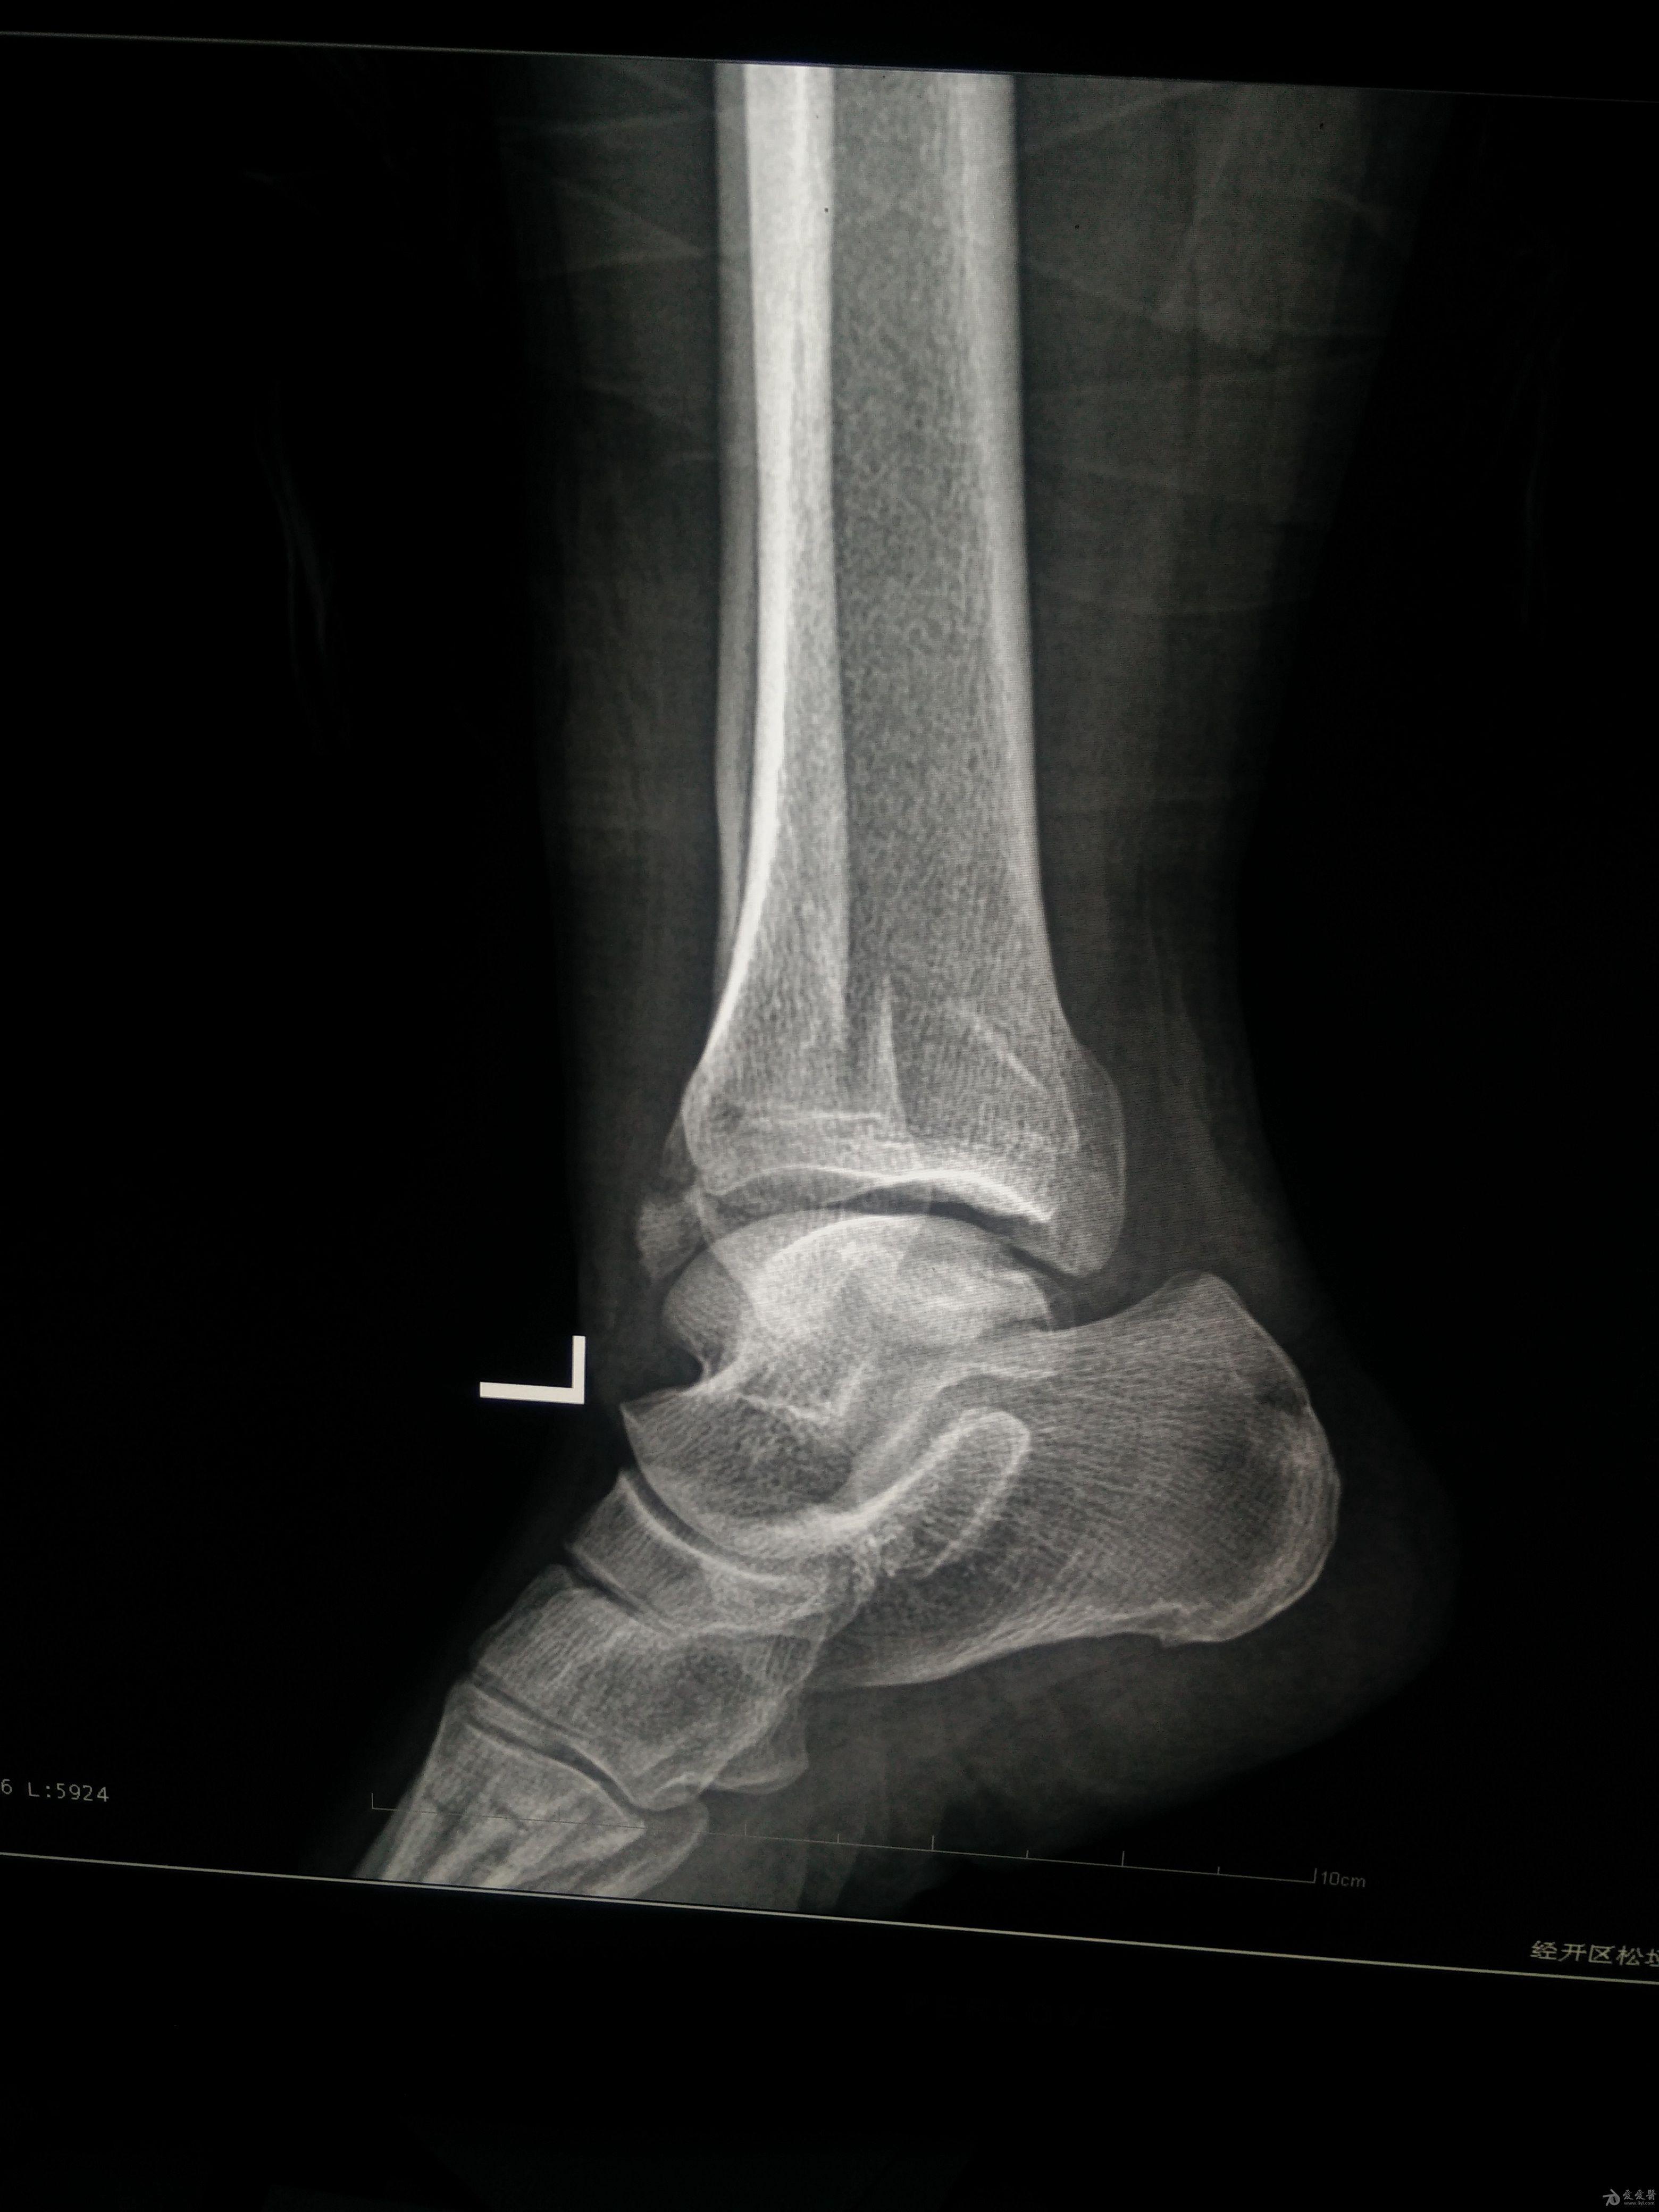

左三踝骨折手术治疗

患者女,外伤后左踝关节活动受限1小时入院,

入院后查体:左踝关节肿胀,活动受限,行DR及左踝关节CT检查,如下图,手术待肿胀消退后行手术治疗,目前愈合良好,请问问各位老师,好久可以下地呀, 下胫腓联合镙钉3个月取呀,